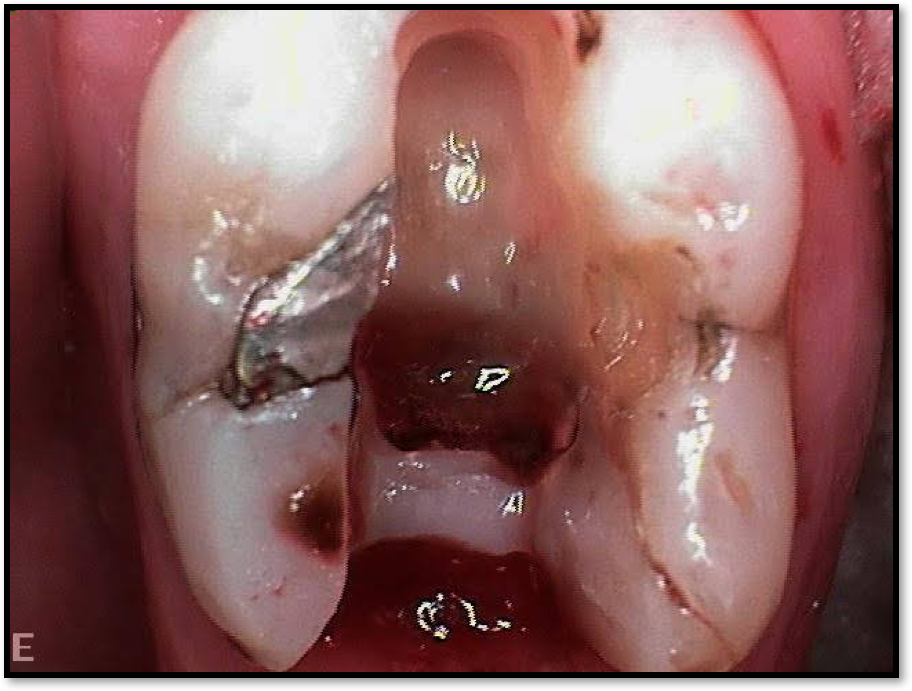

Fig 2. Minimal walls.

Figure 2

Figure 2 shows a situation where the clinician excavated the tooth of a patient with decay, and it pulped out. The buccal and lingual walls were intact; however, the walls were minimal, and there were still fragments of amalgam and cracks. If the clinician prepared this tooth after building it up, the clinician would lose all the good tooth structure that was left. This tooth would likely need a post.